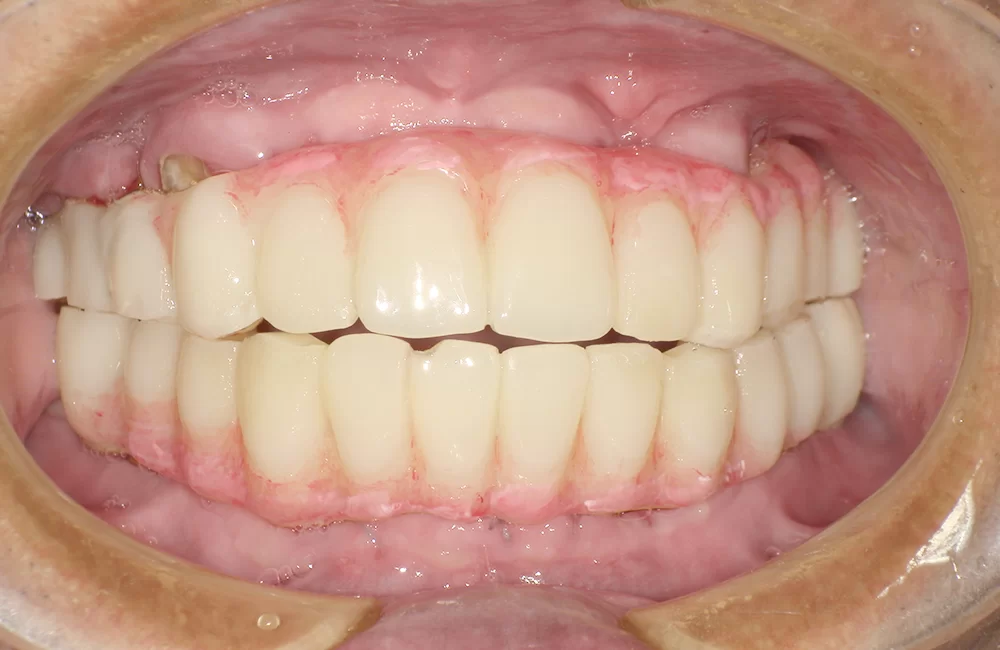

• 治療後